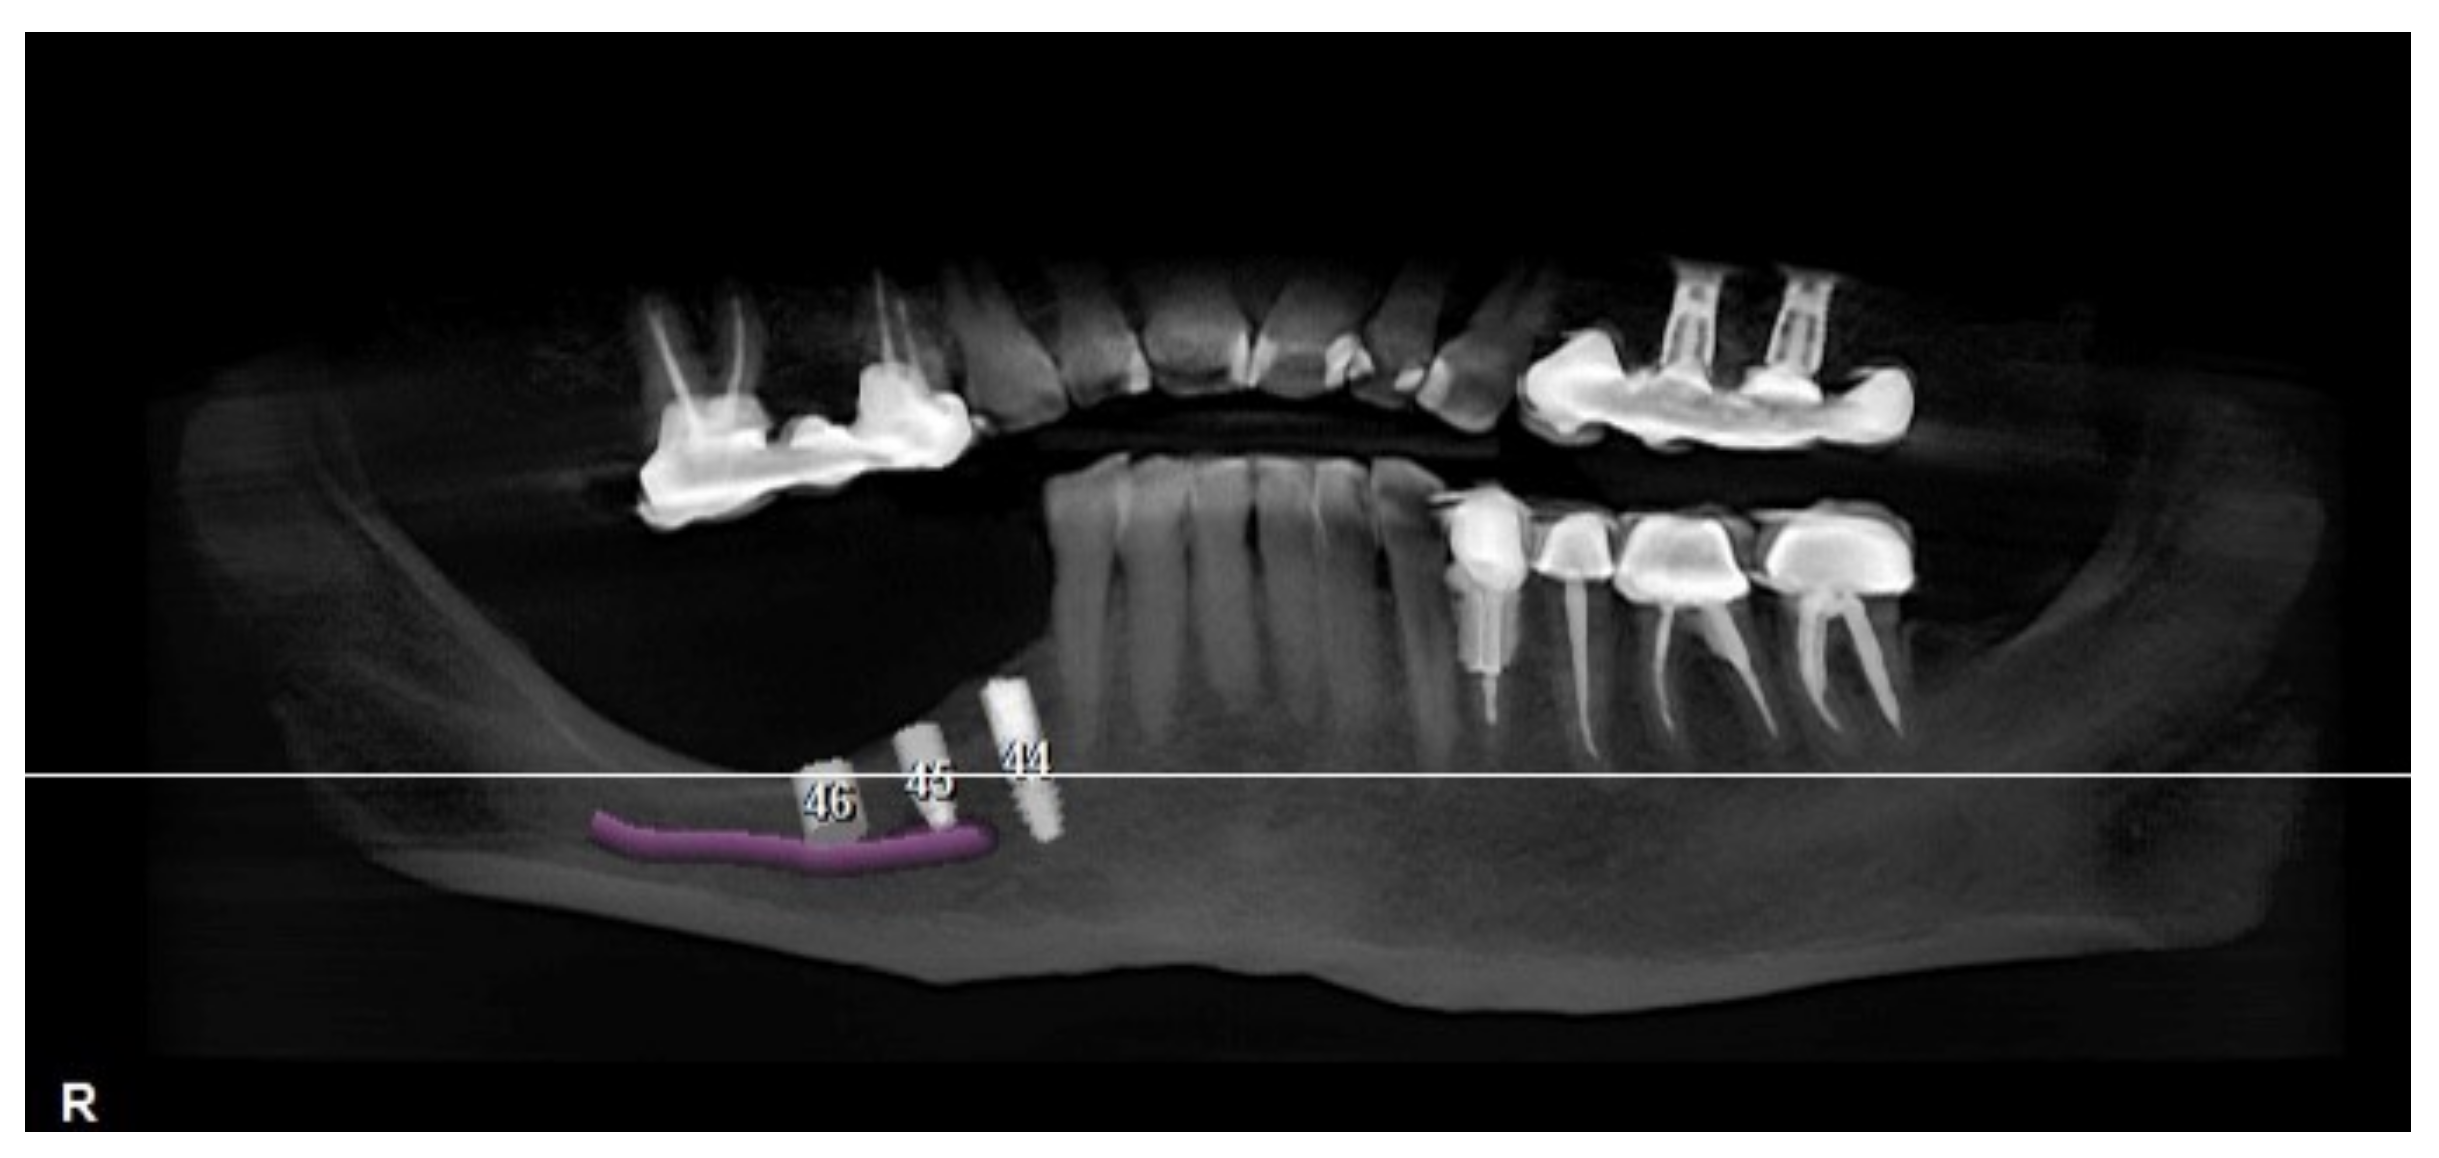

A CBCT scan was made with an initial setup for guided surgery, demonstrating a bone height less than 4 mm from the mandibular canal (Figure 2 and Figure 3a,b).

Figure 2.

Panoramic radiograph showing the implant planning and nerve position.

Figure 3.

Position of the CBCT slice (a) showing the exact location of the canal (b).